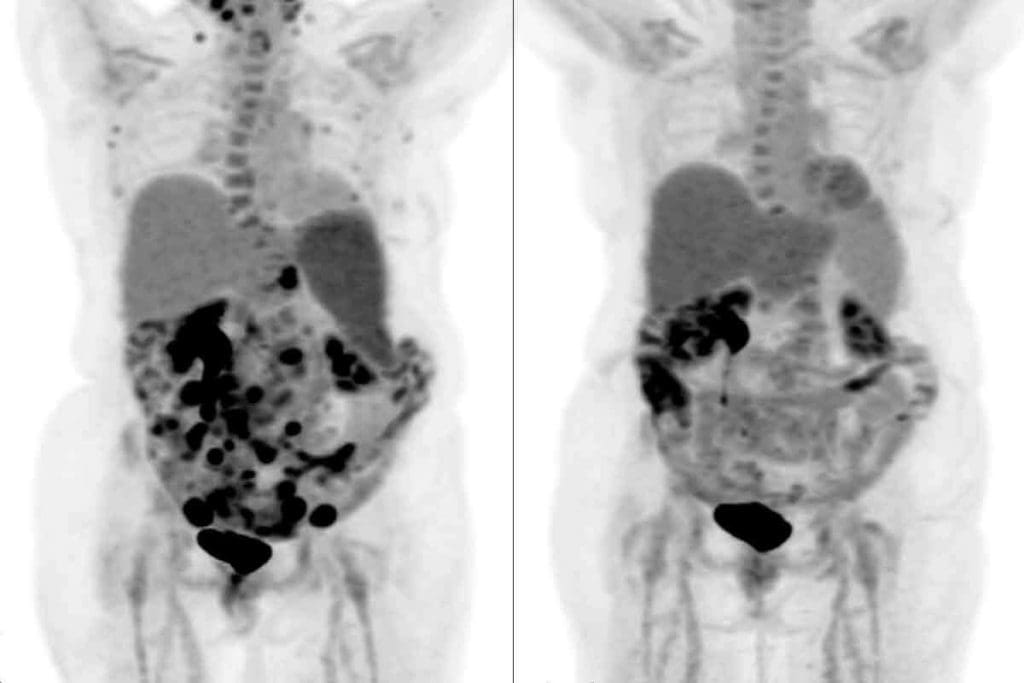

Visual Representation of Tumors on PET Images

The Warburg effect makes cancer cells take up a lot of 18F-FDG. This shows up as bright spots on PET scans. These spots mean there’s cancer.

Characteristics of tumors on PET images include:

- High contrast between tumor and surrounding tissue

- Clear delineation of tumor boundaries

- Ability to detect metabolically active tumors

By understanding the Warburg effect and how it affects 18F-FDG uptake, we can see how PET imaging helps in finding cancer.